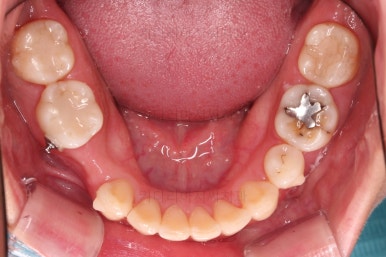

초진 시 입안의 모습인데요.

왜 그런지 비밀이 풀리는 것 같죠?

윗니는 한 쪽이 치아 2개가 결손이면서 유치가 하나 남아있고요.

아랫니는 한 쪽은 1개, 반대편은 2개 치아가 결손이었습니다.

도합 5개의 치아가 결손이었는데요.

결손 위치의 갯수가 위아래 좌우 다 달라서 중앙선이 맞을래야 맞을 수가 없는 상황이었죠.

결손치아 주위 치아들은 쓰러지고 비틀어져 있어서 장기적으로 좋지 못한 상황이었고요.

좀 더 디테일하게 윗니 작은 앞니 1개가 왜소치아라서 치아 크기도 맞지 않은 상황이었습니다.

이번 환자분도 임플란트 2개로 마무리 하기로 계획을 세웠습니다.

결손이 없는 부위에 추가적으로 발치 1개를 더 하고요.

나머지 부위는 적절하게 공간을 모은 뒤에 치아 갯수가 너무 부족한 부분만 선별적으로 임플란트를 하기로 했죠.